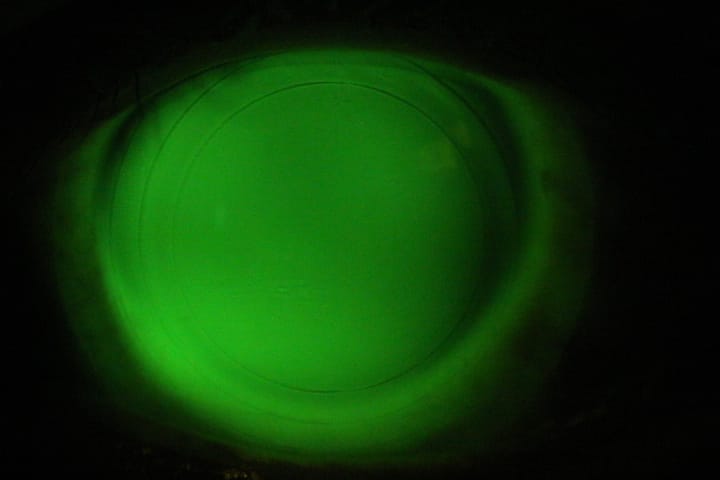

Lente escleral en curva intermedia deficiente.

Zona escleral ajustada